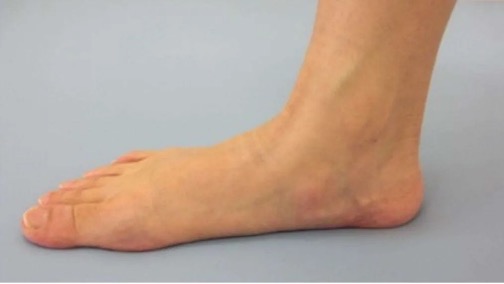

门诊遇到一患者,女,15岁,学生,因“左踝及足疼痛1年余”,来我门诊就诊,询问病史患者1年前出现左踝及足疼痛,行走或起步时疼痛明显,休息后可见稍缓解。查体示双侧纵横足弓消失,左踝及足背轻微肿胀。根据症状体征,诊断为“扁平足”。

扁平足,顾名思义,是指足弓扁平或消失,这是一种常见的足部畸形。其主要症状包括脚内侧缘痛或后跟痛,走远路乏力等。然而,扁平足的危害远不止于此。它可能导致运动受限,甚至引起足部其他关节以及踝关节、膝关节、髋关节的连锁反应,如发生炎症、变形等。这些连锁反应不仅会增加患者的疼痛感,还可能影响正常的行走和站立姿势,严重时甚至可能影响日常生活。

扁平足的检测方法主要有两种:足印法和影像学检查。足印法简单易行,通过观察足印最窄区与足长的比例,可以初步判断是否存在扁平足。影像学检查则更为精确,通过足部X线检查,可以测量足弓角度,明确足弓结构,从而准确判断是否存在扁平足。